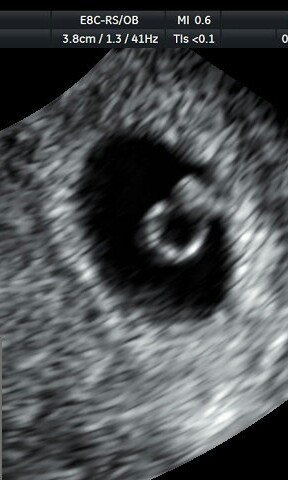

Napewno odezwe sie jutro po wizycie i badaniach z krwi. Nie podchodzę do tego jako szczescia, tylko do wydarzenia ktore rozpoczyna caly lancuch zdarzen. Jestem juz po 3 naturalnych ciazach, a zadna nie dotrwala do etapu serduszko, wrecz zakanczaly sie zanim sie jeszcze zaczely. Do tego jeszcze porzadnie przeziebiona jestem. I jak juz sie znowu do was odezwalam, to juz "pochwale sie" moim ostatnim znanym mi wynikiem krwi. AMH=0,2 brak słów